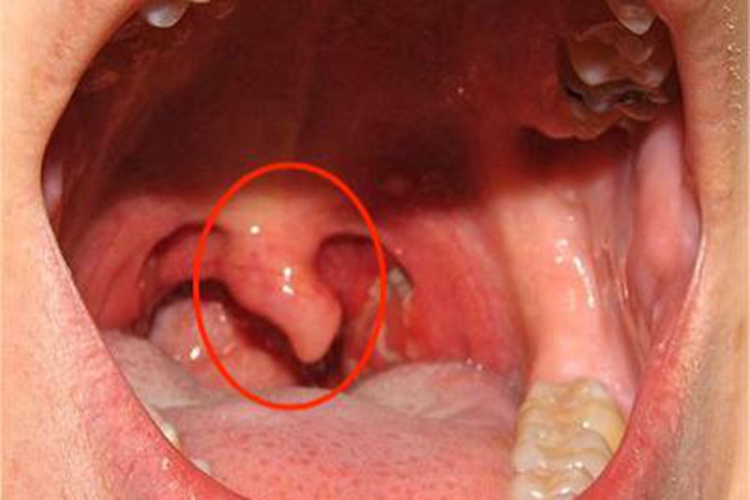

急性咽炎起病较急,先有咽部干燥、灼热,继有明显咽痛,吞咽时尤重,有时可伴有发热、头痛、食欲减退和四肢酸痛等。检查可见口咽部黏膜呈急性弥漫性充血、肿胀,表面可见黄白色点状渗出物,可伴随悬雍垂水肿。